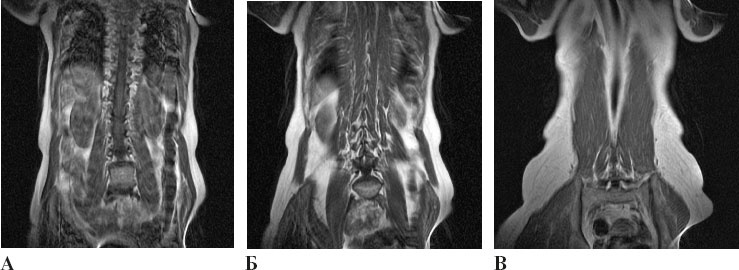

Рисунок 31. В прогибах спины подвздошно-поясничная мышца (слева), мышцы, поддерживающие позвоночник (в центре), и квадратная мышца поясницы (справа) оказывают тянущую, а следовательно, стимулирующую нагрузку на тела поясничных позвонков спереди (А) и сзади (Б), косвенно с боков через нижние ребра (В) и под множеством углов между ними (Б).